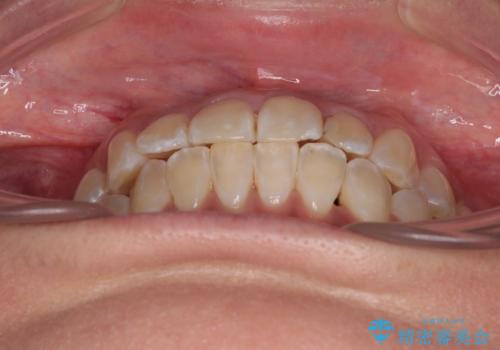

- 上下の前歯のでこぼこを気にして来院された患者様です。

職場の都合により、表側のワイヤー装置や着脱作業が頻繁なマウスピース矯正は困難とのことで、全く目立たない裏側矯正装置を用いて口元を整えることとしました。

途中転勤や出産があり、通院できない期間が長くありましたが、無事に歯列を整えることができました。